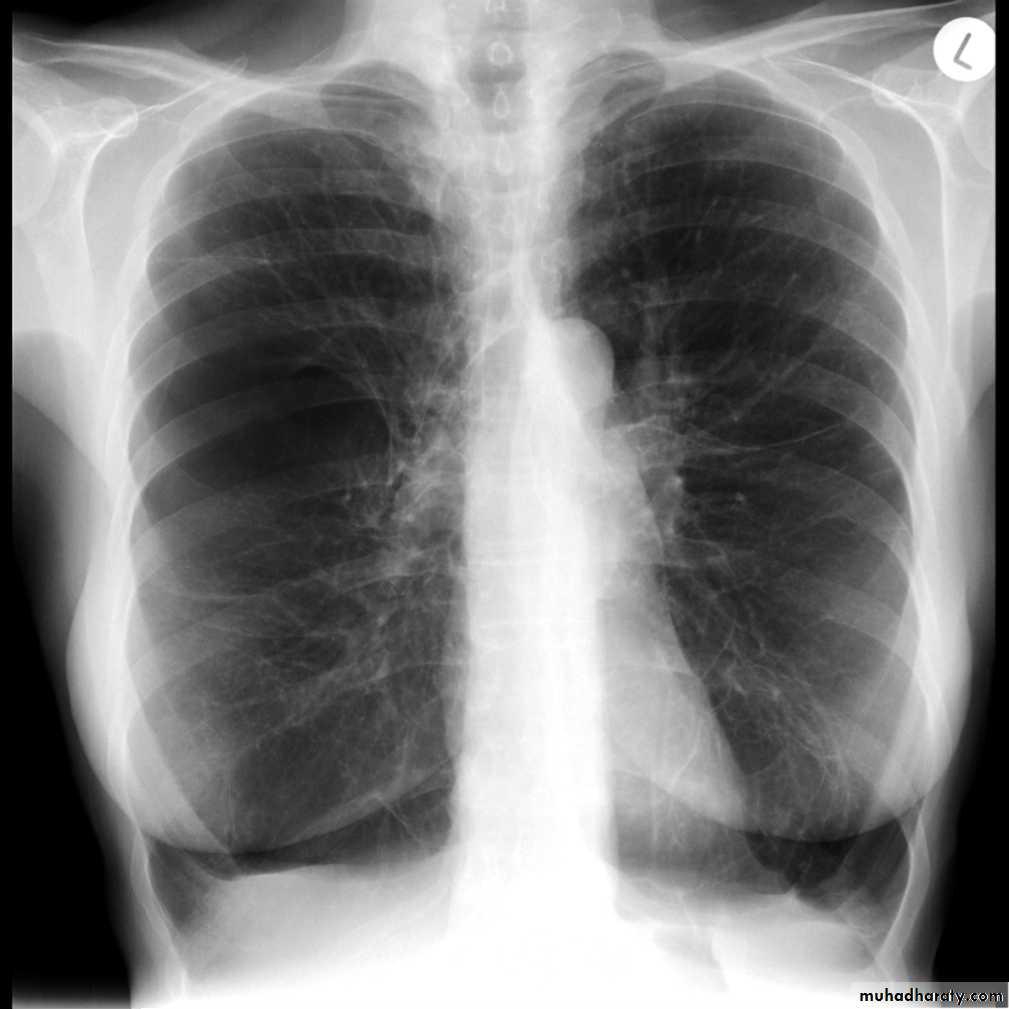

A pneumothorax is, when looked for, usually relatively easily appreciated. Typically they demonstrate:

visible visceral pleural edge see as a very thin, sharp white line

no lung markings are seen peripheral to this line

the peripheral space is radiolucent compared to adjacent lung

the lung may completely collapse

the mediastinum should not shift away from the pneumothorax unless a tension pneumothorax is present